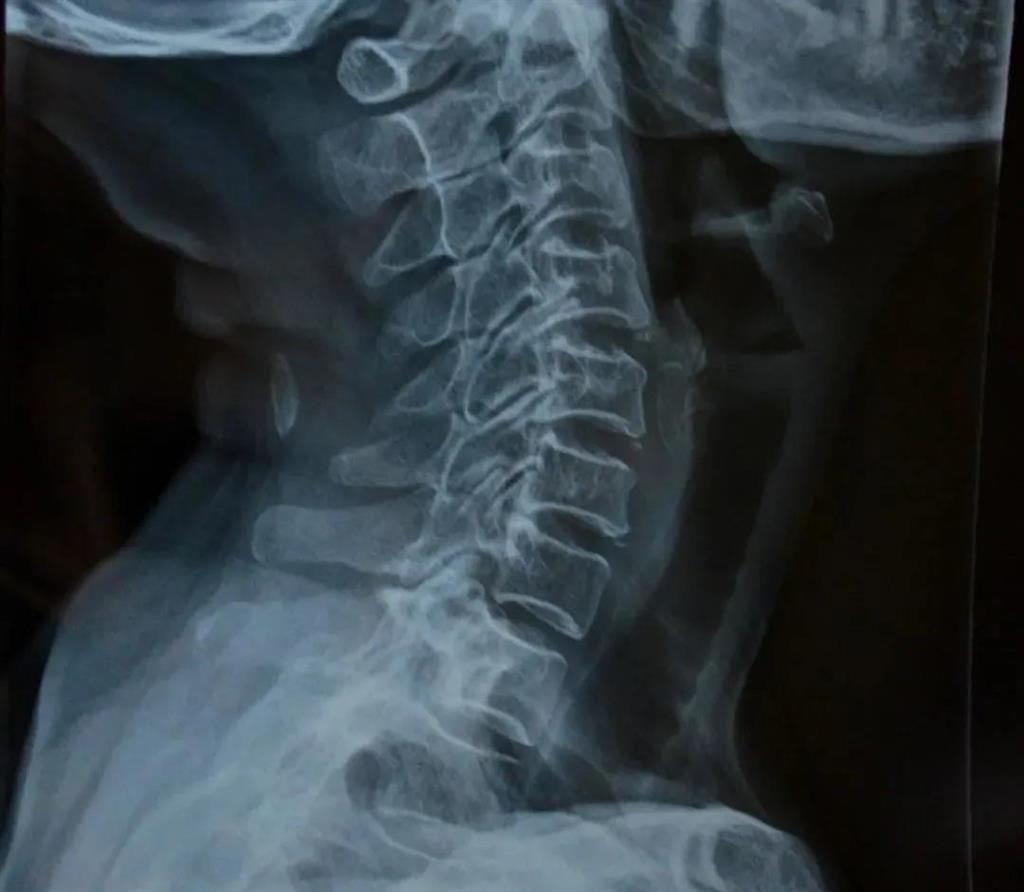

頸椎X片是頸椎病的常規檢查方法,常表現為頸椎正常生理曲度消失或者是反張,椎間隙狹窄,椎管狹窄,椎體后緣骨贅形成,在頸椎的過伸過屈位片上還可以觀察到頸椎節段性不穩定。

——圖源網絡

可得信息:

(1)判斷頸椎的大體形態、曲度、穩定性;

(2)判斷骨頭結構是否出現破壞的情況;

(3)是否出現骨質增生或先天畸形的情況。